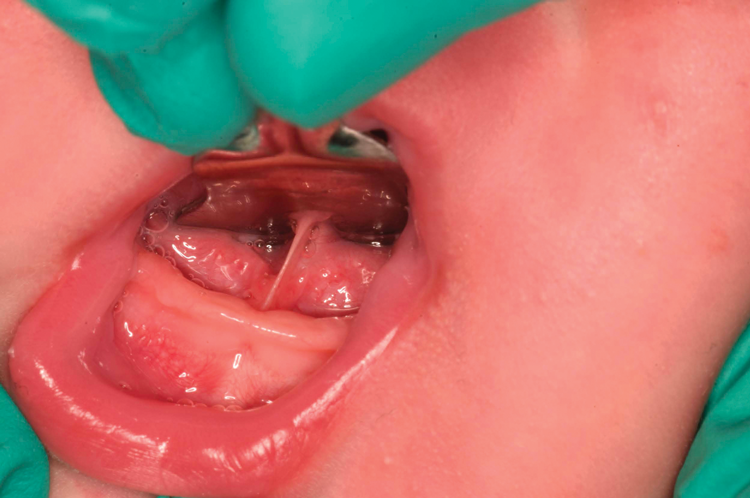

To perform laser frenectomy on an infant, have the mother sit and firmly hold the baby on her chest while an assistant provides evacuation. A swaddle can be of great assistance in maintaining a stationary child. Infant wraps and restraints can be beneficial as well. Therefore, having these available is highly recommended. Utilizing a high-volume evacuator attachment with slotted sides can help to ensure that excess water is efficiently removed during these surgeries (Figure 1). Have an assistant cover the child's eyes with a soft towel while holding the head as calmly as possible. For lingual frenectomies, retraction of the tongue is achieved with a grooved director with polished edges, which facilitates visual identification of the frenulum, lingual veins, saliva ducts, and salivary tubules (Figure 2).

(2.) Retraction of the tongue is achieved with a grooved director with polished edges, which facilitates visual identification of the frenulum, lingual veins, saliva ducts, and salivary tubules.

Figure 2

(3.) Preoperative and postoperative retracted views of a case involving an excessive tongue-tie that was treated with laser surgery.

Figure 3

(3. AND 4.) Preoperative and postoperative retracted views of a case involving an excessive tongue-tie that was treated with laser surgery.

Figure 4